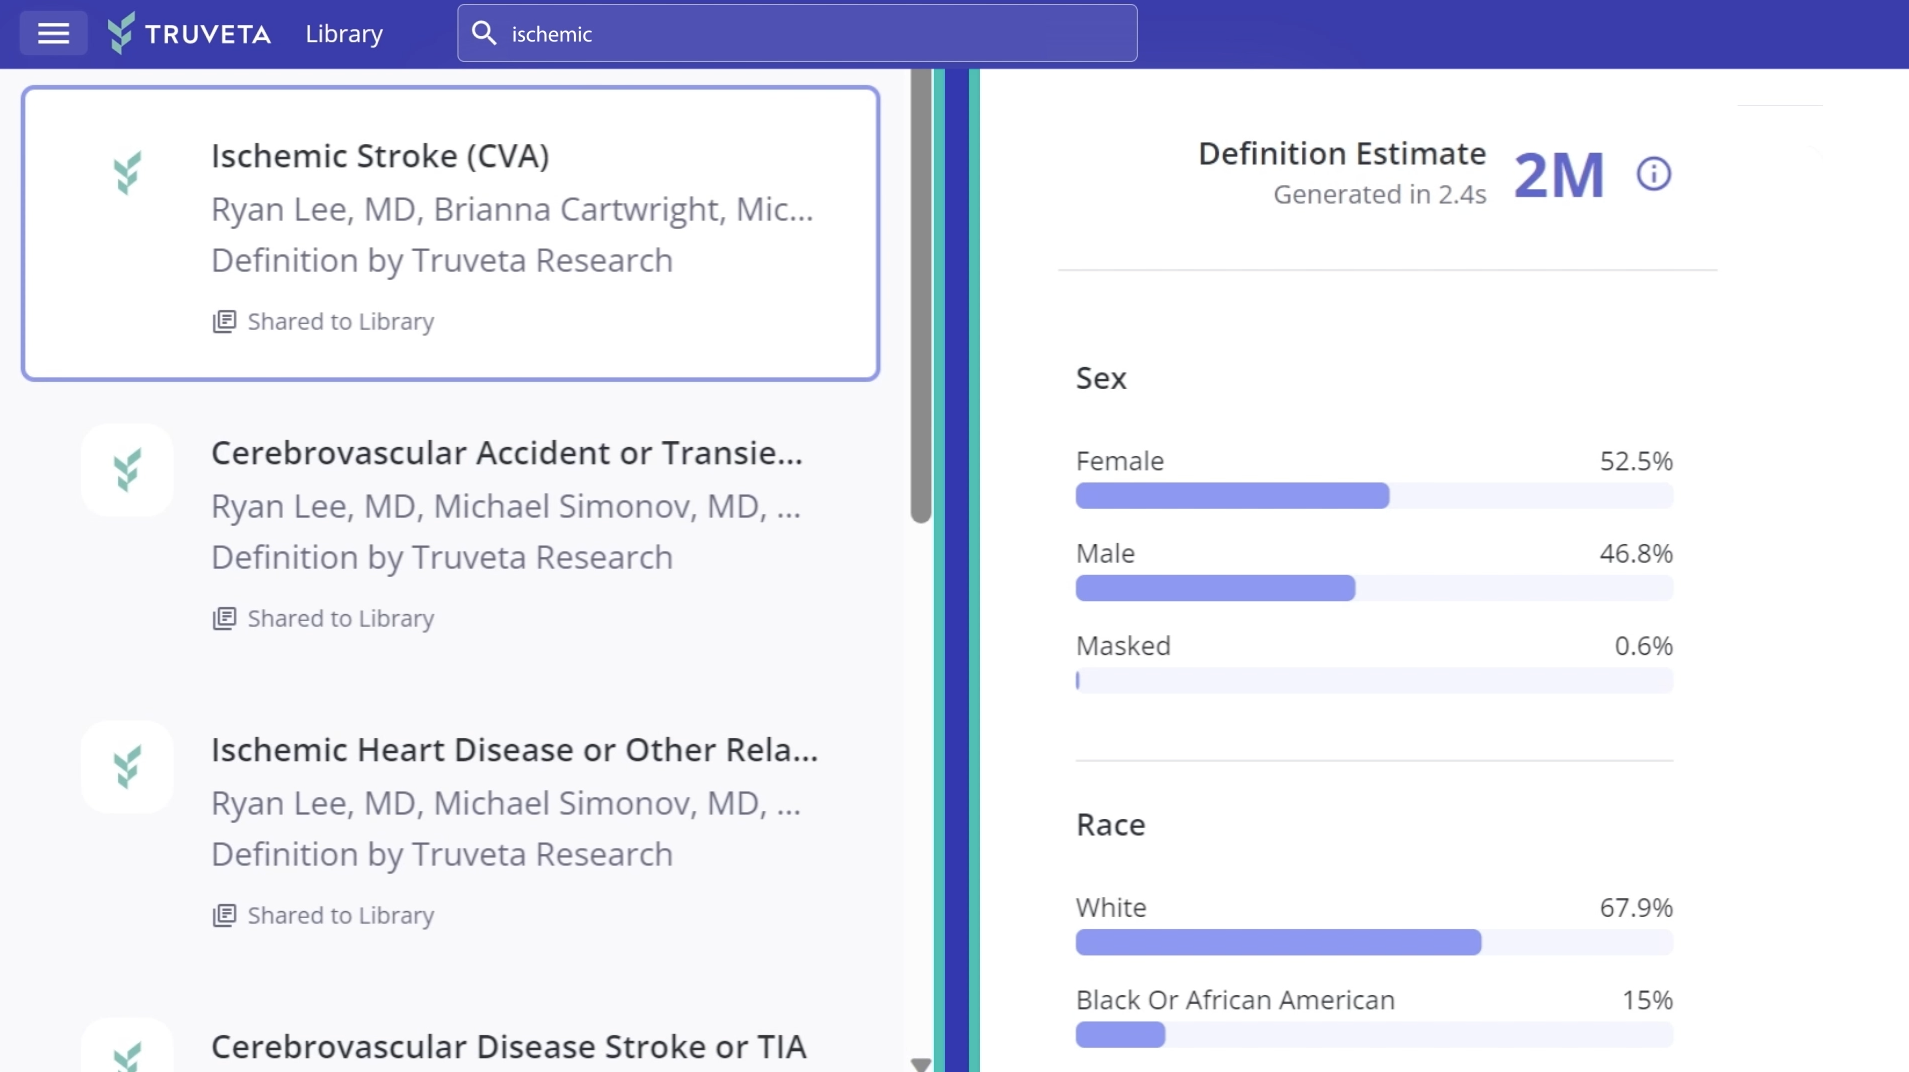

Study medical images integrated with longitudinal EHR data

Images are part of Truveta Data, which includes complete EHR data for more than 120 million patients, linked with claims, SDOH, and mortality data.

Data are representative of inpatient and outpatient care across the US, and are updated daily from members, cleaned with clinical expert-led AI, and de-identified with industry-leading privacy and security technology.